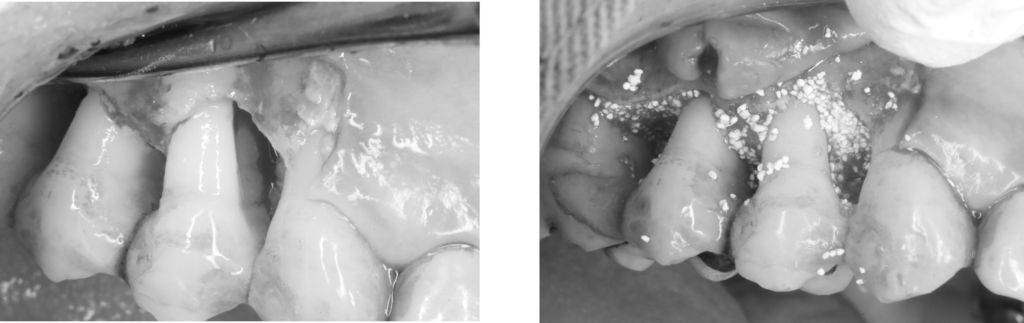

歯肉を開いて歯肉の中の歯根面に付着している歯石や骨(歯槽骨)が溶けている中の不良肉芽(正常でないない軟組織)を徹底的に除去し、

再生材料と人工骨と填入し、縫合しました。